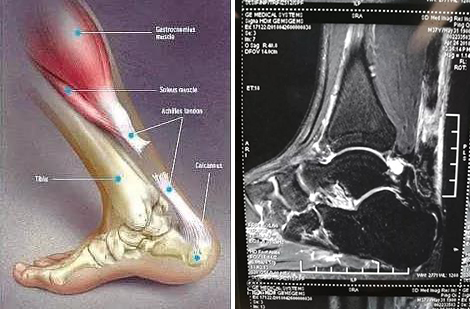

跟腱断裂通常在30~50岁的男性群体中发病率较高,平均年龄约35岁,其发病率在发达国家为每年每2~10/10万人,男女发病比例约为4:1至20:1。跟腱断裂在人体肌腱断裂部位发生率位居第三位。患者常诉足跟后方有棒击感,随即出现提踵无力,无法完成蹬地、跳跃等动作,表现为行走困难及推进无力并伴有跛行,跟腱处出现凹陷。最易明确诊断的检查方法是通过挤压小腿后方肌肉来判断腓肠肌-比目鱼肌复合体的连续性,即Thompson征阳性。怀疑跟腱断裂的患者,可通过B超或MRI检查来明确。

跟腱断裂示意图 跟腱断裂MRI表现

患者于某,因打球致左足跟部疼痛肿胀1天入院,查体左足跟部肿胀,按之空虚感,Thompson试验阳性,左足跖屈无力。既往体健。MRI显示左跟腱断裂(见上图)。入院完善检查后,给予左跟腱断裂微创修复术,术中情况见下图,术后踝关节跖屈位短腿石膏固定6周,更换跟腱靴6周后正常下地活动。未见并发症发生,患者非常满意。